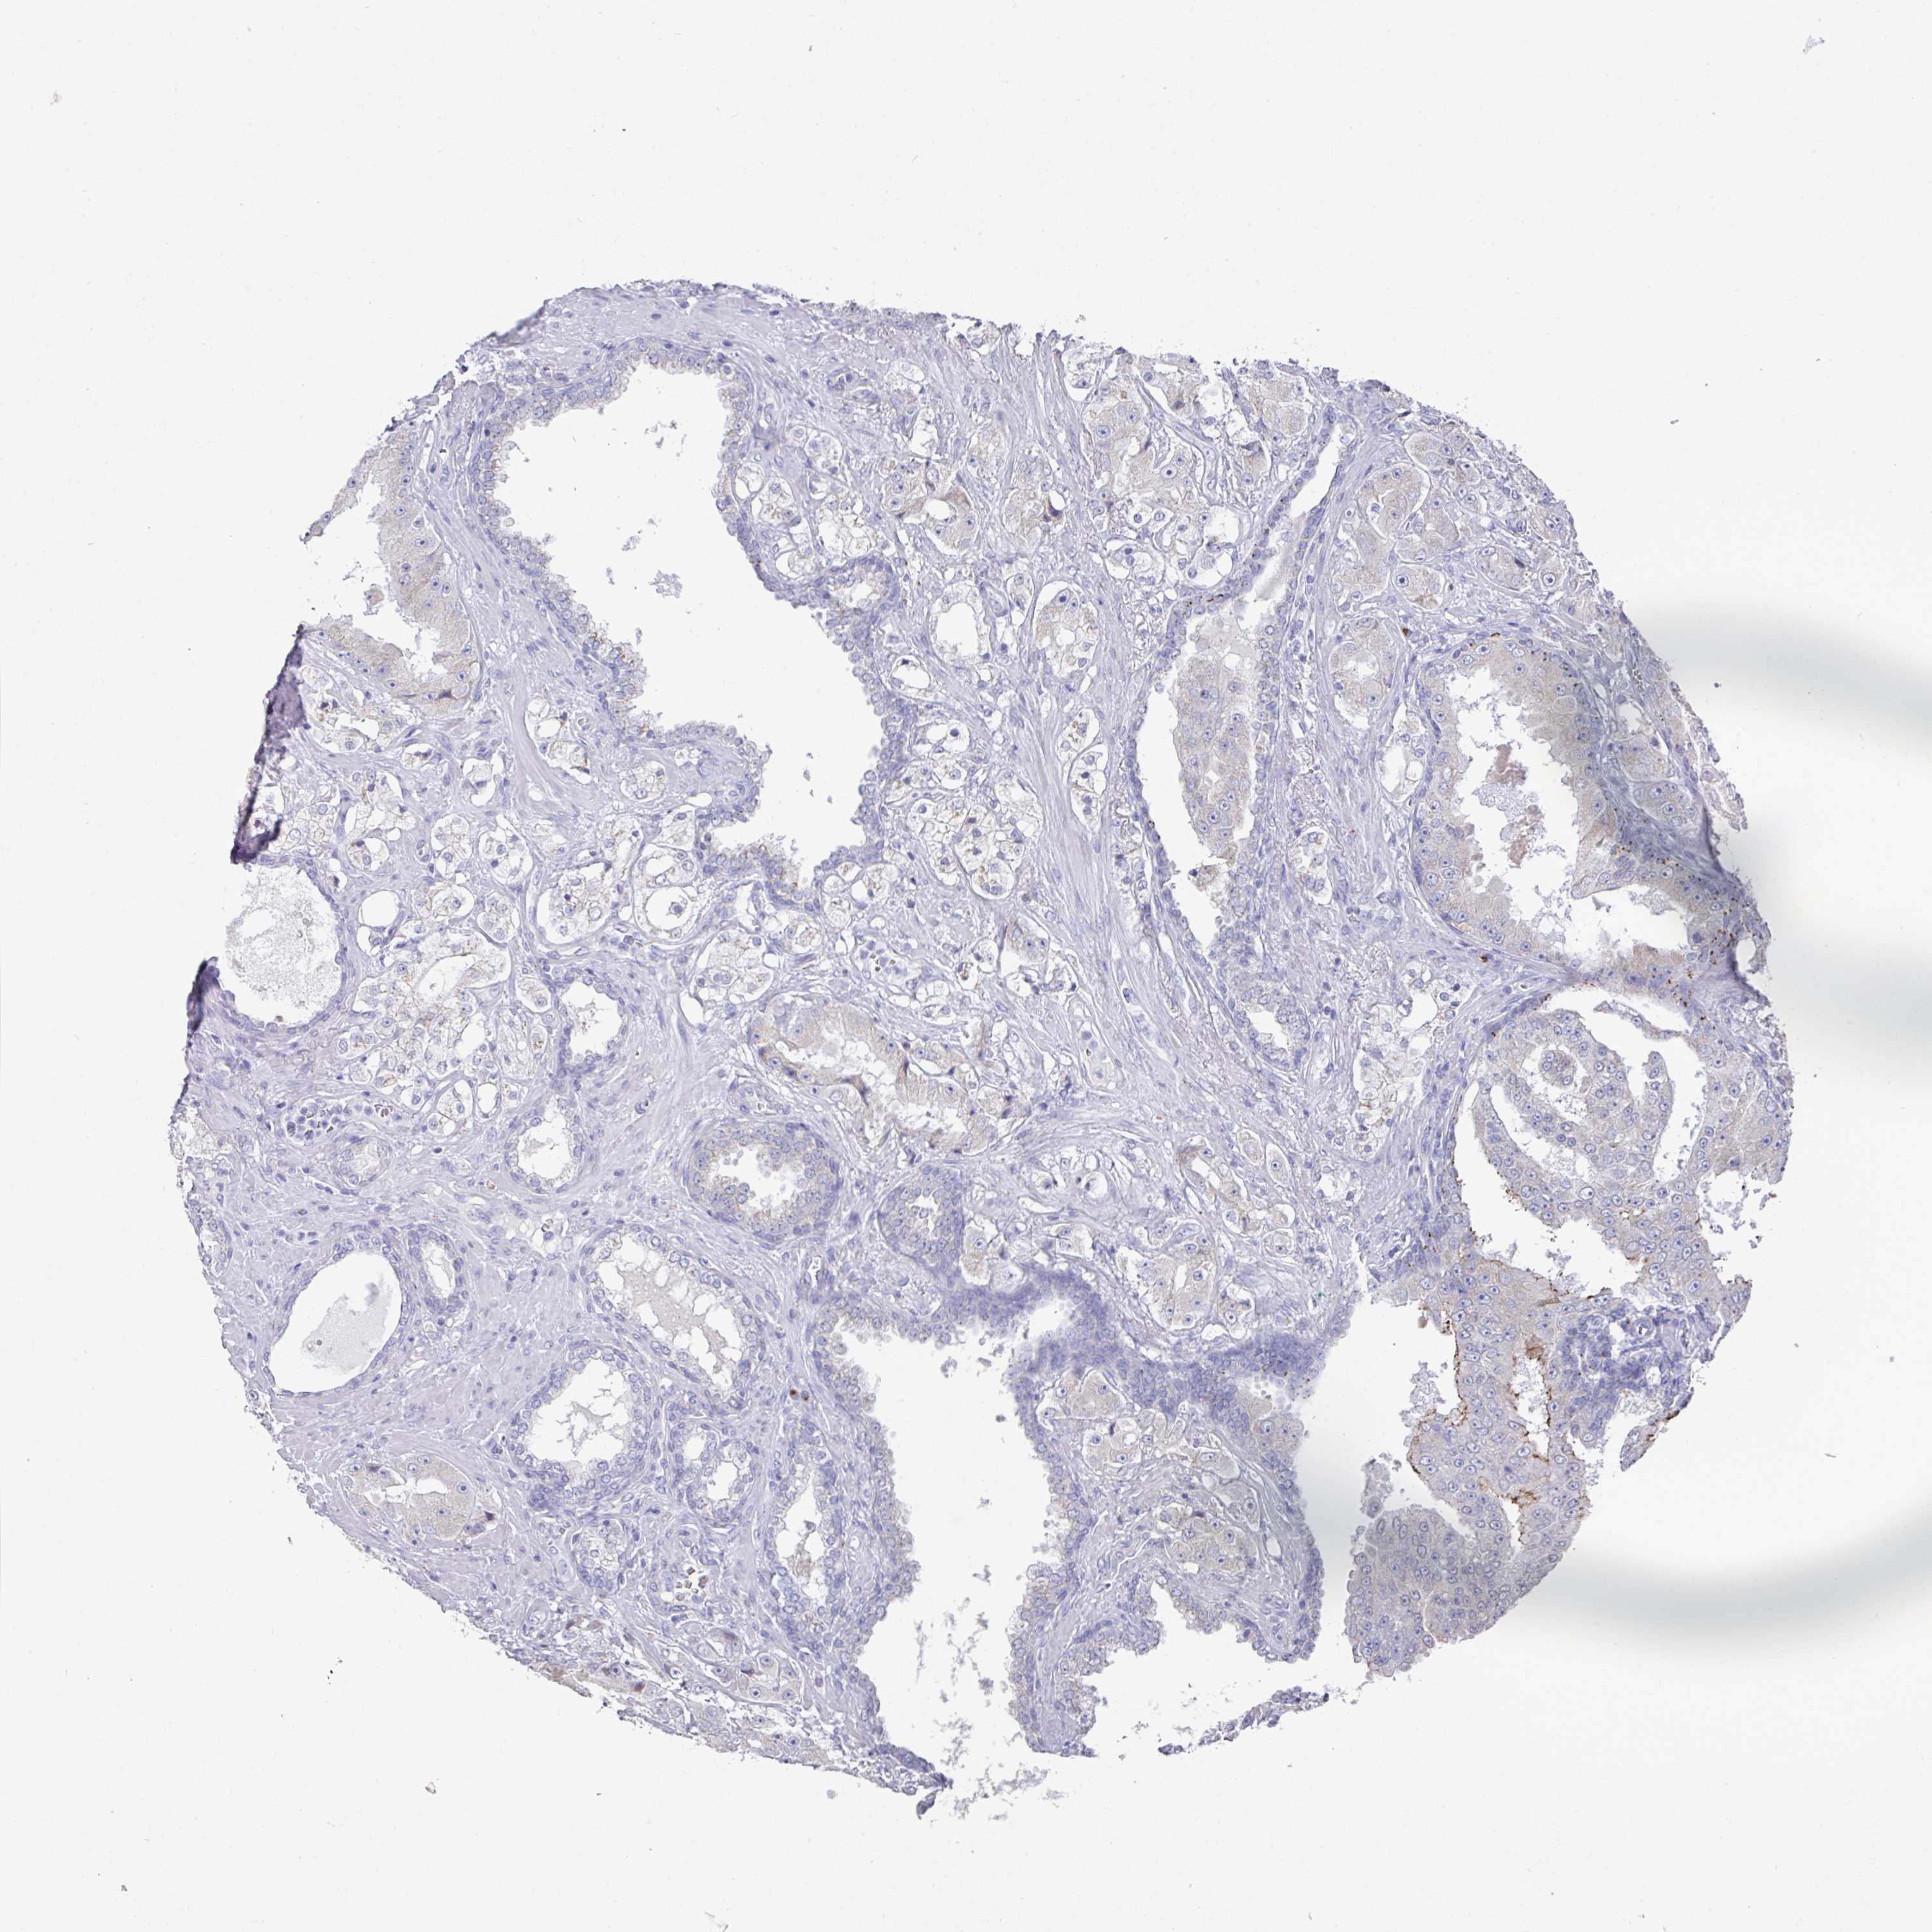

PROSTATE CANCER - Protein expressioni

A mouse-over function shows sample information and annotation data. Click on an image to view it in a full screen mode. Samples can be filtered based on level of antibody staining by selecting one or several of the following categories: high, medium, low and not detected. The assay and annotation is described here.

Note that samples used for immunohistochemistry by the Human Protein Atlas do not correspond to samples in the TCGA dataset.

Antibody stainingi

Antibody staining in the annotated cell types in the current human tissue is reported as not detected, low, medium, or high, based on conventional immunohistochemistry profiling in selected tissues. This score is based on the combination of the staining intensity and fraction of stained cells.

Each image is clickable and will lead to virtual microscopy that enables deeper exploration of all samples and also displays staining intensity scores, fraction scores and subcellular localization as well as patient and tissue information for each sample.

Antibody HPA053954

Staining

High

Medium

Low

Not detected

Intensity

Strong

Moderate

Weak

Negative

Quantity

>75%

75%-25%

<25%

None

Location

Nuclear

Cytoplasmic/membranous

Cytoplasmic/membranous,nuclear

Adenocarcinoma, High grade

Adenocarcinoma, Low grade